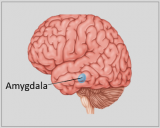

A neuroanatomia é o ramo da anatomia que estuda a anatomia do sistema nervoso, ou seja, a estrutura, a função e a organização do sistema nervoso. O sistema nervoso é um dos sistemas mais complexos do corpo humano e inclui o cérebro, a espinal medula, os nervos periféricos e os gânglios nervosos. A neuroanatomia preocupa-se com a forma como estas estruturas estão ligadas entre si, como os sinais são transmitidos entre as células nervosas e como as diferentes partes do sistema nervoso trabalham em conjunto para controlar as funções corporais e cognitivas. Os neuroanatomistas utilizam técnicas de imagiologia avançadas, como a ressonância magnética (MRI), a tomografia por emissão de positrões (PET) e a microscopia para visualizar as estruturas e funções do sistema nervoso.